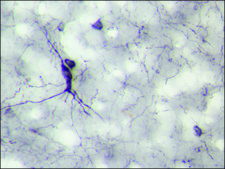

: suitable using suitable for IHC on rat brain perfused with 4% paraformaldehyde

Neuropeptide Y (NPY), a 36-amino acid peptide amide, is a major regulatory neuropeptide widely distributed in the mammalian central (CNS) and peripheral nervous systems (PNS). NPY belongs to the pancreatic polypeptide family of peptides which are characterized by a common tertiary structure. Within this family, an intestinal peptide hormone, peptide YY (PYY), is most closely related to NPY. In the CNS, NPY is involved in regulation of blood pressure, memory processing, circadian rhythm, and stimulation of food intake. In the PNS, NPY has potent vasoconstrictor activity and acts as a neurotransmitter/neuromodulator of sympathetic neurons and adrenal glands. NPY is one of the most abundant peptides found in the CNS, widely distributed in the brain. High levels of NPY are present in the cerebral cortex, amygdaloid nuclei, hippocampal formation, and hypothalamus. In the PNS, NPY is found mainly in sympathetic neurons that innervate vascular smooth muscle, heart, and urogenital tract. The biological actions of NPY in the brain and periphery are mediated by at least two different NPY receptors, designated Y1 and Y2 receptor subtypes.

Anti-Neuropeptide Y (NPY) antibody produced in rabbit has been used in:

• single-labeling immunocytochemistry

• immunofluorescence

• immunostaining